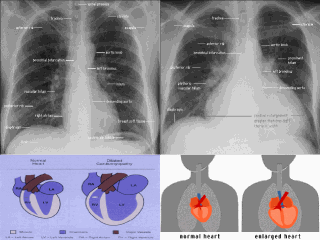

Dilated and normal hearts XR.